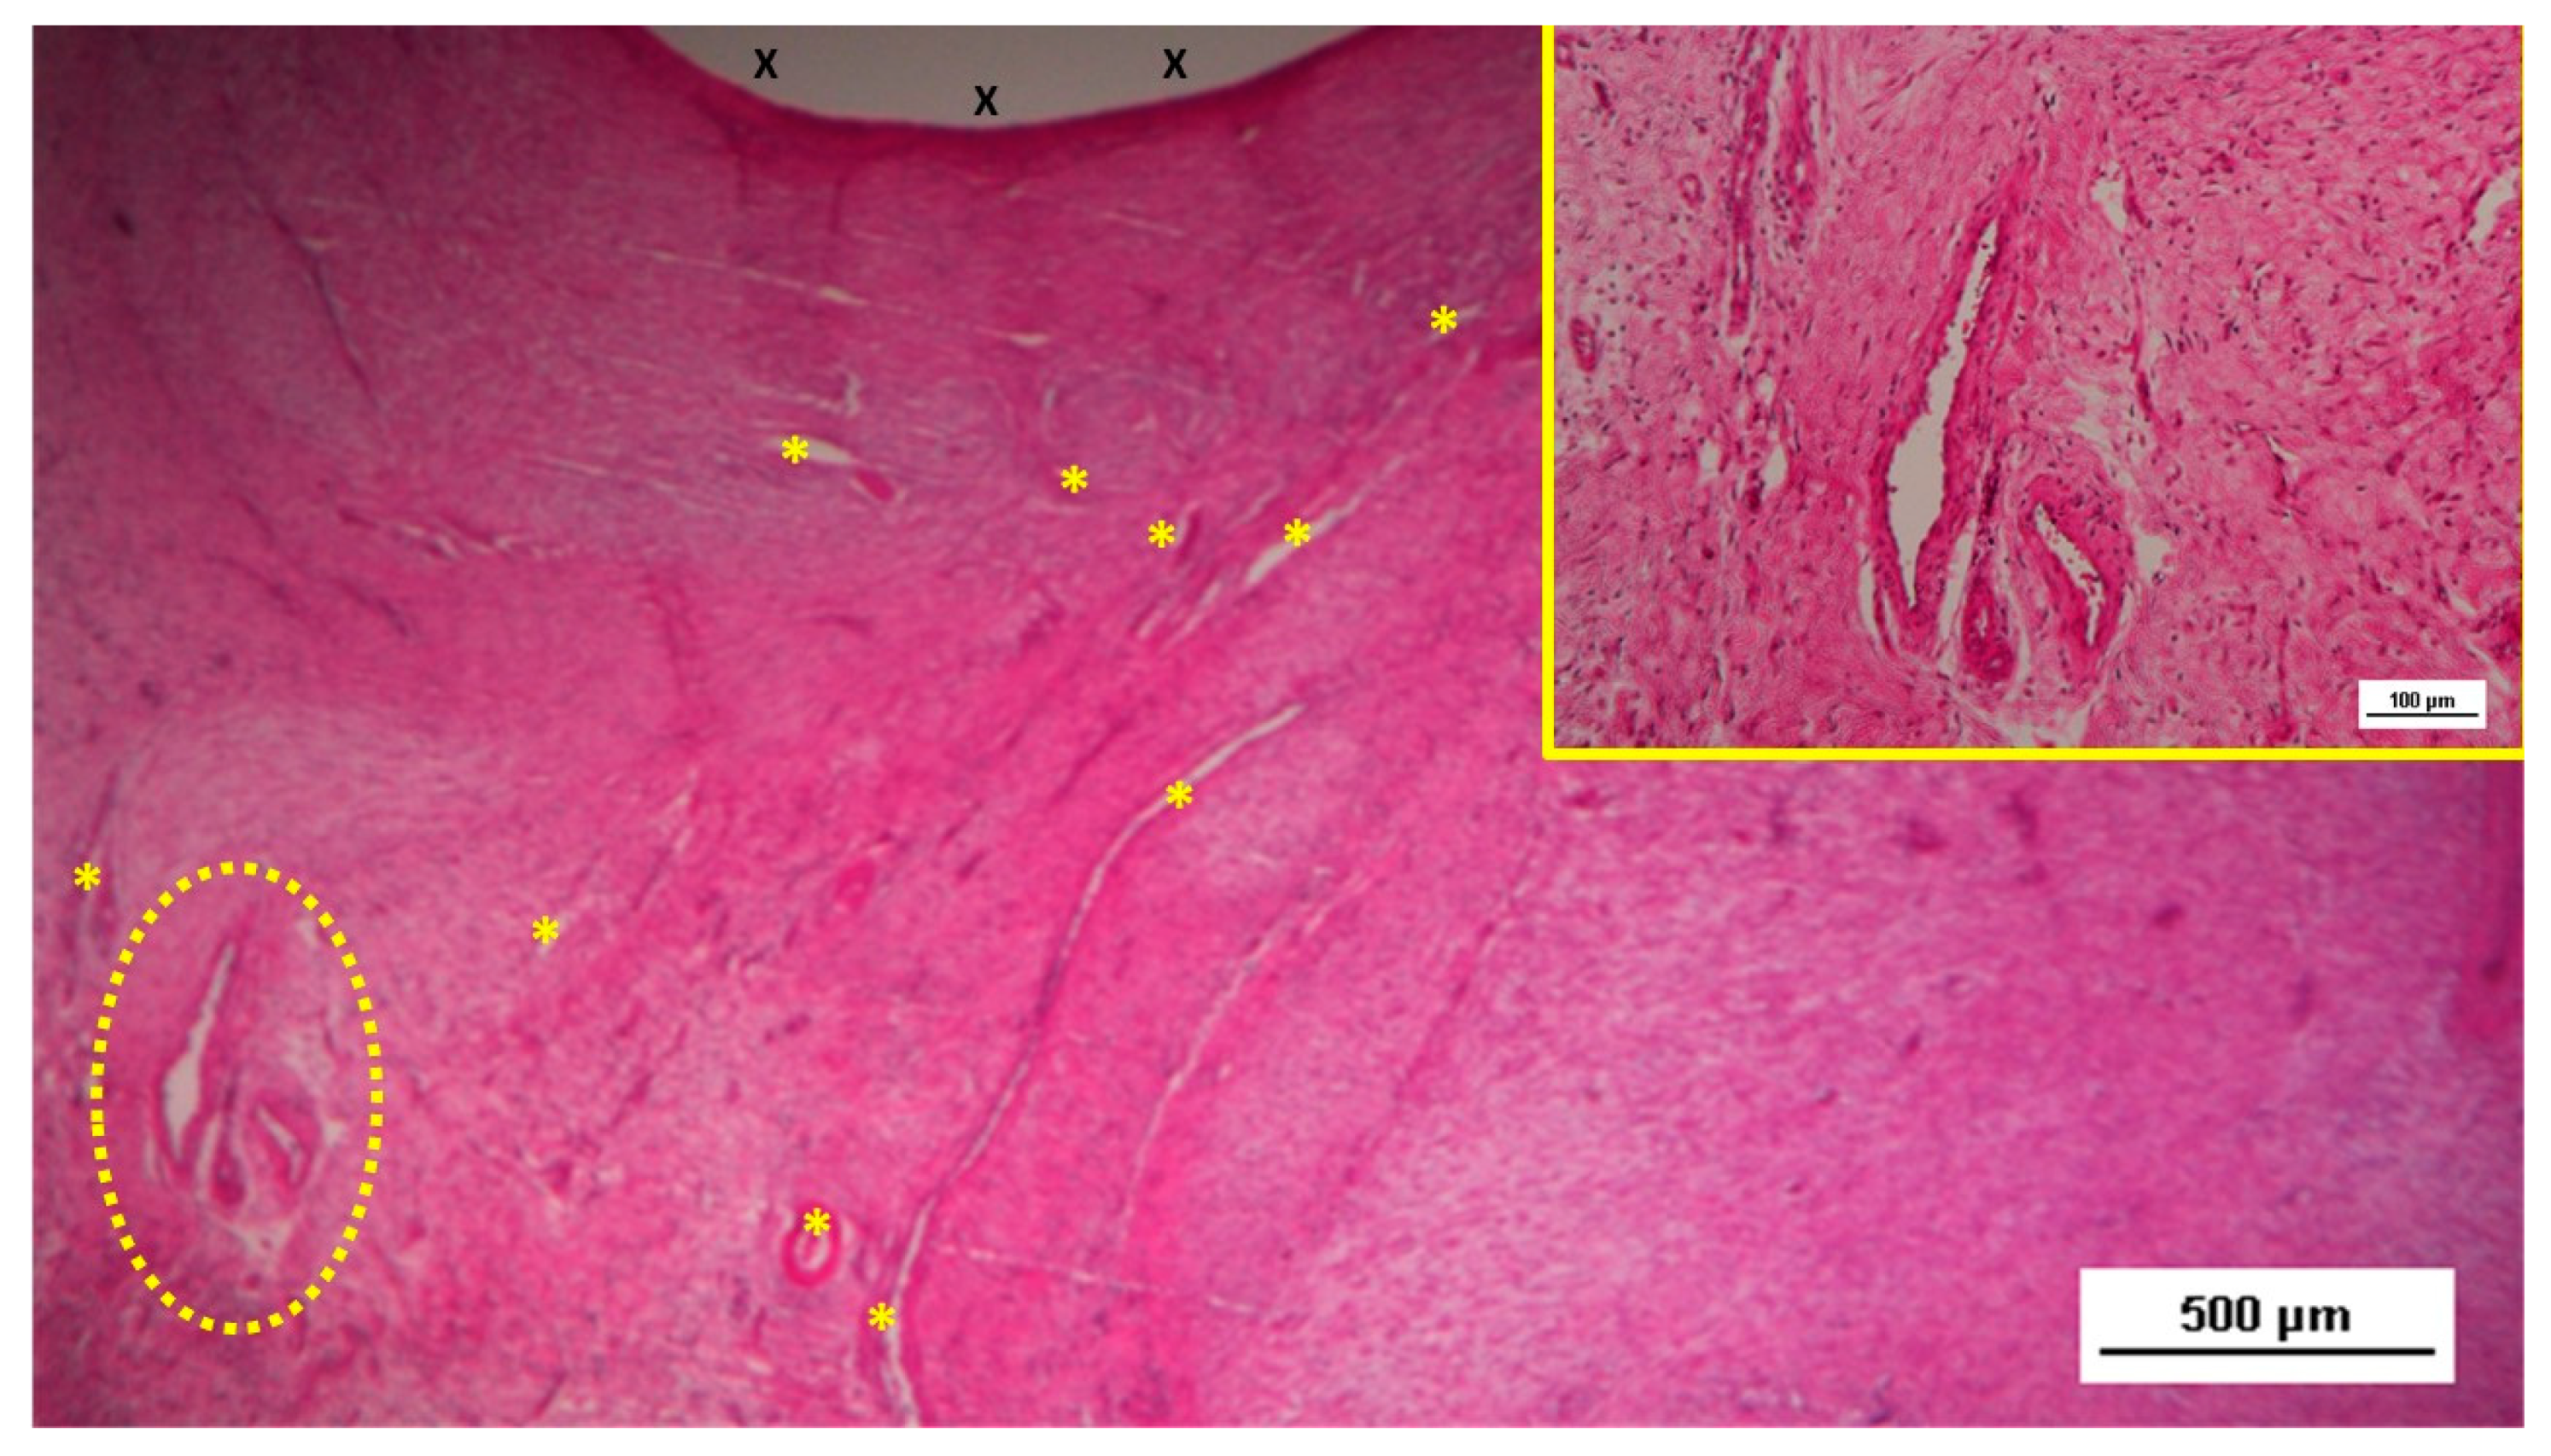

Figure 4. Biopsy taken five weeks post-implantation from the 3D scaffold of the S&S device. Near the TPE fabric (X), no inflammatory reaction is present, but numerous vascular structures (*)—primarily immature veins—are visible. A yellow circle highlights a cluster of arterial elements in the early-stage of development. The inset (right upper corner) offers a detailed view of the arterial structures with developing muscular layers. HE 25X (main image) and HE 100X (inset).

Two pathologists evaluated the tissue samples and the related histological sections in blinded manner regarding the postoperative period. Tissue samples taken from the scaffold of the S&S device during the short-term period (3-5 weeks post-implantation) revealed an abundant presence of early-stage vascular clusters near the scaffold material, with minimal inflammatory response observed (Figure 3, Figure 4, Figure 5 & Figure 6).

In the mid-term period (3-4 months post-implantation), H&E staining showed a significant presence of vascular structures within the S&S device. Notably, in this postoperative period no signs of inflammatory response against the fabric of the S&S device could be evidenced. The arterial structures displayed advanced development, with well-defined endothelial and muscular layers, while the adventitia was properly enveloping the vessels. Similarly, the veins exhibited noticeable structural maturation compared to the earlier period (Figure 7, Figure 8 & Figure 9).